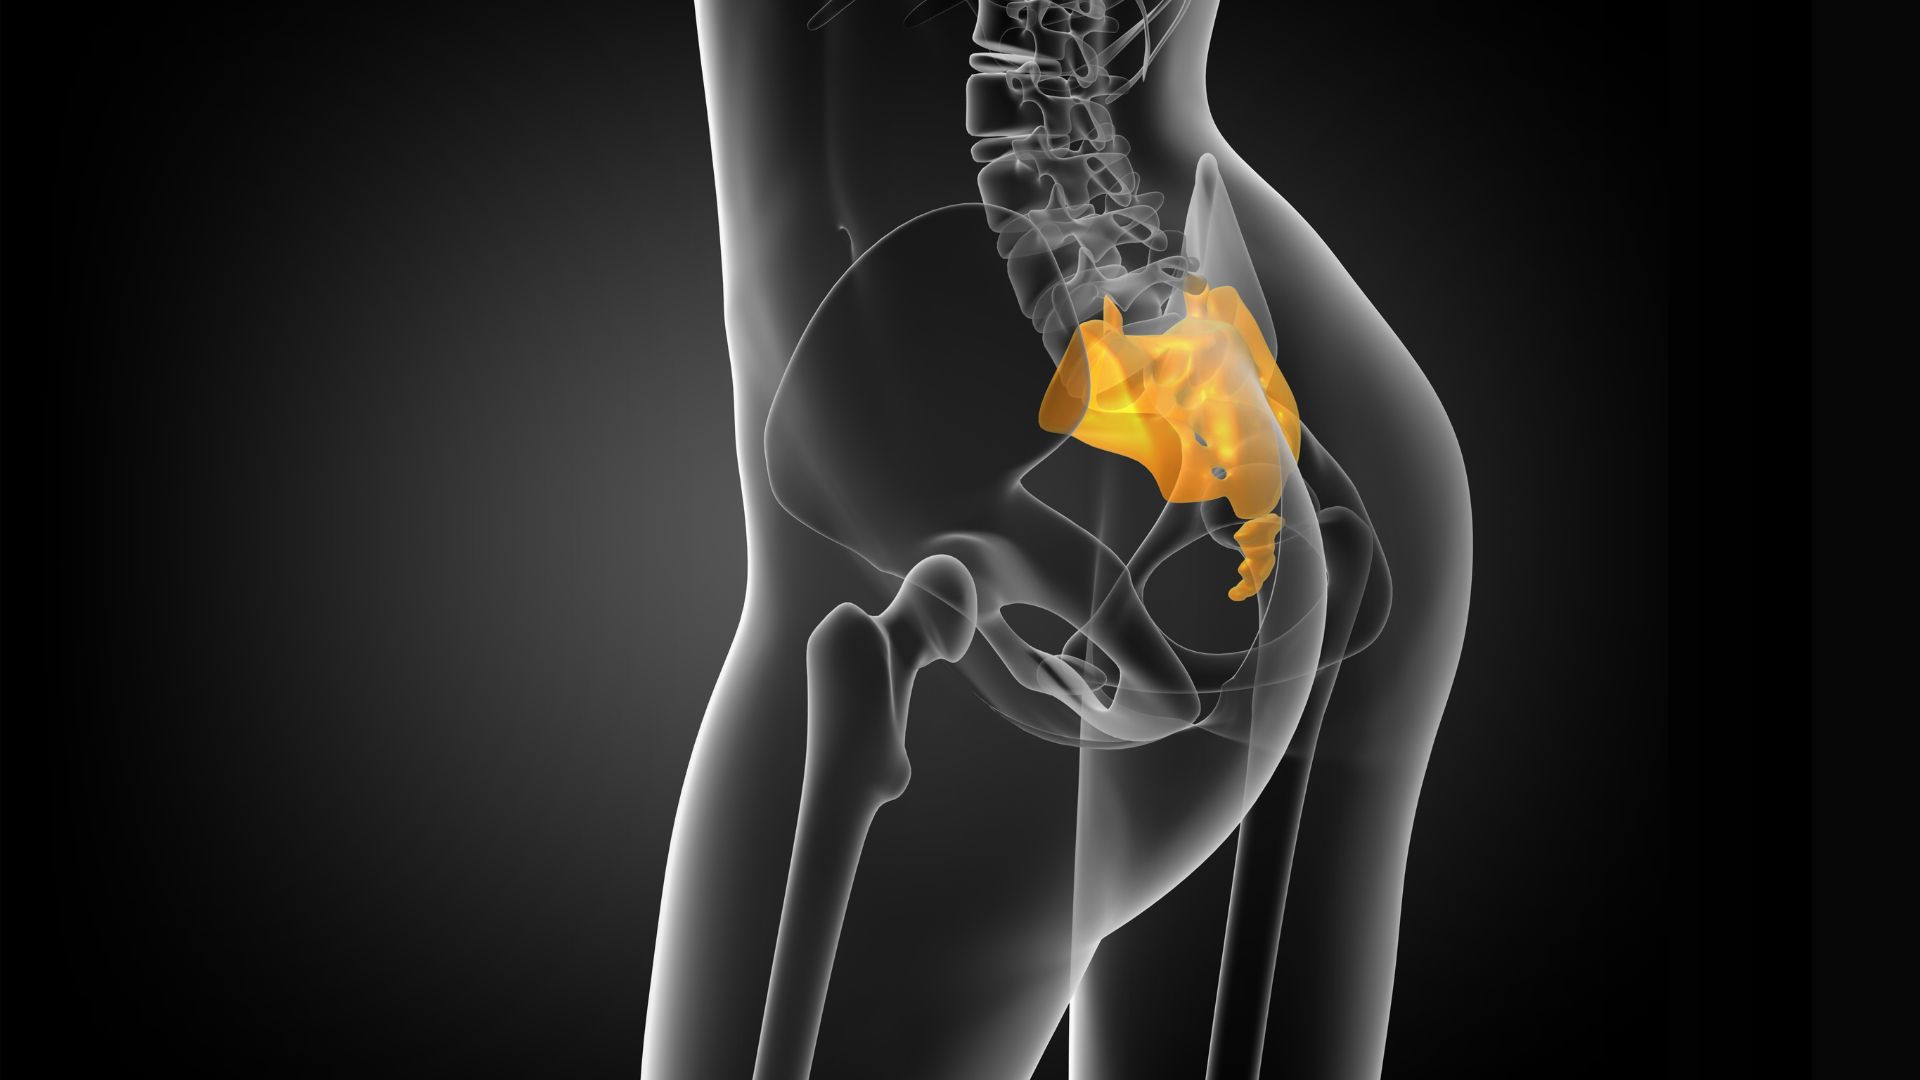

https://www.youtube.com/embed/RlpuIrQvToc Low back pain often results from various forms of sacroiliac dysfunction. Of the ten or so ways the sacrum can become stuck “crooked” between